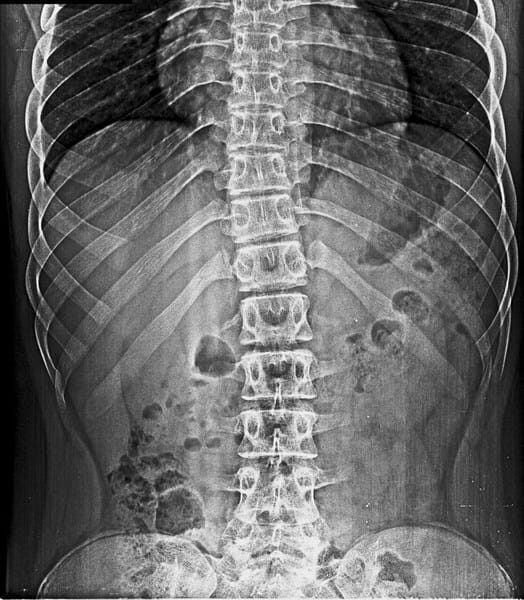

Mi sobrino tiene 16 años, pesa 74 kilos y mide 1,77. Se le realizo recientemente un chequeo medico y uno de sus Rx arrojo una escoliosis, que aunque el medico indico que era una leve a moderada, no indico un tratamiento especifico, tampoco indico recomendaciones para mejorarla o al menos para que no se acentué más la deformación. Quería saber su opinión y saber en cuantos grados aproximado tiene la escoliosis y que deporte es el más recomendable para no afectar más la columna.